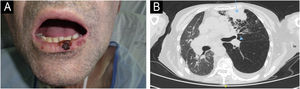

O primeiro caso (fig. 1A‐B) era de um paciente masculino, de 54 anos, receptor de TCTH alogênico (alo‐TCTH) para leucemia mieloide crônica três anos antes, que apresentou CECC no lábio inferior. O paciente foi inicialmente tratado com cirurgia com margens livres de lesão. Após três meses de seguimento, ele desenvolveu metástases nos linfonodos regionais, pulmonares e ósseas, confirmadas por histopatologia de biopsia guiada por ultrassom, biopsia transbrônquica e biopsia guiada por TC, respectivamente. As lesões progrediram rapidamente, e foi escolhido o tratamento paliativo, ocorrendo a morte em seis meses. O segundo caso (fig. 2A‐B) era paciente masculino, de 63 anos, receptor de TCTH autólogo (auto‐TCTH) para mieloma múltiplo cinco anos antes, que apresentou CECC na comissura esquerda dos lábios. No diagnóstico, o paciente apresentava metástases em linfonodo regional (confirmado por histopatologia de biopsia guiada por ultrassom) e pulmonares (confirmadas por histopatologia de biopsia transbrônquica) e derrame pleural de grau acentuado. Em virtude de sua má condição basal (ECOG3) e a pedido explícito do paciente e de sua família, foi escolhido o tratamento paliativo resultando em morte menos de três meses após o diagnóstico.

Paciente Número 1. (A) Carcinoma espinocelular cutâneo medindo 1,3 × 1cm é observado no lábio inferior. (B) A tomografia computadorizada axial revela massa consistente com metástase pulmonar no segmento anterior do lobo superior esquerdo (seta azul), juntamente com metástase paratraqueal esquerda associada (ponta de seta azul).